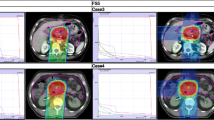

Evaluated plans for pancreatic adenocarcinoma (A) and for glioblastoma (B) patient cases are displayed in Fig. 1. The prescription dose and target optimization goals were achieved as shown in biological dose maps and the dose volume histograms (DVHs) outlined in panels (D). LETd maps, LETd profiles and LETd-volume histograms (LVHs) demonstrate that the maximum LETd for IMPT plans is placed outside of the target volume and extends into normal tissues. For the GTV, LETd values were around ∼40–65 keV/µm. In order to increase LETd in the target, LETd optimization feature was also investigated in Fig. 1 (IMPTLET). As observed from the LETd distribution, the inclusion of LETd-boosting allows LETd-escalation at the GTV, while having a minimum impact on the target dose coverage (see DVH for the clinical target volume, CTV). IMPTLET allowed an increase in the GTV minimum LETd from 55.1 keV/µm to 87.1 keV/µm, and from 38.4 to 48.6 keV/µm, for the glioblastoma and pancreatic adenocarcinoma cases, respectively. However, LETd optimization comes at the expense of an increase in the beam’s entrance biological dose. For the glioblastoma patient, for example, there could be an increase of up to 30% in the biological dose delivered to the skin directly exposed to the entrance channel. Additionally, for IMPTLET plans, normal tissue DVH highlights an increase of the volume in the middle range doses (20–30 Gy (RBE)) compared to standard IMPT.

Simultaneously, the LETd escalation is still constrained by the chosen beam arrangement. In scenarios in which two posterior beams are used, as seen in pancreatic cases currently treated at HIT, although IMPTLET raises LETd in the GTV, the high-LETd region is still focused at the distal edge of the tumour volume.

For both glioblastoma and pancreatic cases shown in Fig. 1, SHArc led to an enhancement of the maximum LETd in the GTV up to at least 125 keV/µm, while the minimum GTV LETd values were 46.1 keV/µm and 47.2 keV/µm, respectively. The plotted LETd profiles further demonstrate that the maximum LETd for SHArc plans is concentrated in the central region of the tumour.

Maps of biological dose (DRBE) and LETd for IMPT, IMPTLET and SHArc plans for (A) pancreatic adenocarcinoma and (B) glioblastoma patient cases using carbon ions. For visualisation, the LETd values are displayed with a 5 and 20 Gy low-dose threshold, for glioblastoma and pancreatic cases, respectively. The white lines in the LETd map designate the LETd profiles presented in panel (C). (C) Profiles for LETd are presented highlighting the LETd range within the GTV for both cases. (D) DRBE- and LETd-volume histograms are shown for relevant organs of interest, for the IMPT (full line), IMPTLET (dashed line) and SHArc plans (dotted line). For the DVH plots (top row), the CTV is shown (orange), as well as either the body excluding the PTV or the brain excluding PTV (pink), for the pancreatic and the head case, respectively. In the LVH plots (bottom row), the GTV is shown for both cases (green), as well as the main OAR for each case (red): the gastrointestinal tract for the pancreatic adenocarcinoma and the ventricles of the brain for the case of the glioblastoma. For the pancreatic case, two lines are mostly indistinguishable for the OAR shown in both the DVH and the LVH, due to the nearly overlap between IMPT and IMPTLET volume histograms (i.e., full and dashed lines).

This comes at the cost of a low dose-bath as shown in the normal tissue DVHs. In terms of LETd in the OARs, SHArc could be particularly beneficial for pancreatic adenocarcinoma. In this case, the clinical beam arrangement results in higher LETd values towards the beam’s distal edge, thus directly leading to high LETd in the gastrointestinal tract, which is posterior to the tumour. With SHArc shifting the high LETd towards the tumour’s centre, there is a direct reduction of the near-maximum LETd in the gastrointestinal tract. Specifically, SHArc lowers the maximum LETd in the gastrointestinal tract to 47.5 keV/µm compared to 88.0 keV/µm and 83.0 keV/µm found for the IMPT and IMPTLET plans, respectively. For the glioblastoma case, in which opposite fields are considered as the standard, the reduction of the near maximum LETd in the surrounding OAR, i.e., the brain ventricles, is less pronounced. Nonetheless, there is still an observed decrease in the LETd5%, from 88.4 keV/µm to 79.7 keV/µm.